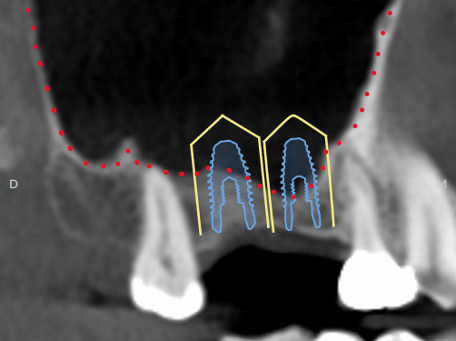

Following a sinus lift procedure described above and 6 months of healing, the patient returned with more than adequate amount of bone for solid implant anchorage below the repositioned sinus floor. The same sized virtual implants are simulated showing the improved situation.

The final CBCT demonstrates the implants were positioned as planned. Note, the metal implants cause a “scatter” artifact outlined in light blue. After 3 months of implant healing, this patient is now ready for teeth to be attached to the implants.